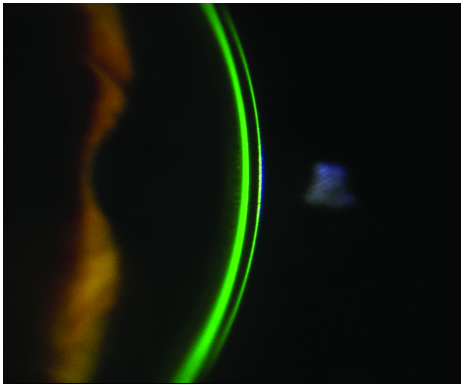

El método tradicional para realizarlo es con instilación de cantidades estandarizadas de fluoresceína o solución de Grant. En la actualidad, existen equipos como el Tearscope (Fig. 10) o el Keratograph (Fig. 11) que permiten realizarlo sin el uso de esos colorantes. A esta forma de realizarlo se le denomina BUT no invasivo.

Figura 10: Tearscope

Figura 11: Keratograph. Imágenes tomadas de la web

del equipo.

Ambos equipos evalúan eficazmente al menisco lagrimal y a su capa lipídica, y el Keratograph realiza además un muy eficaz análisis de las glándulas de Meibomio.